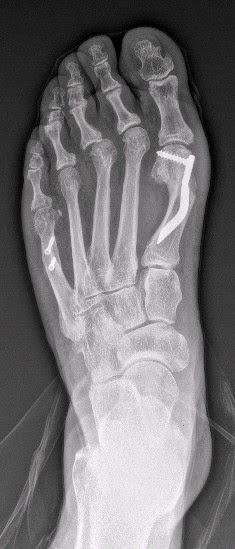

Para ello opté por la realización de una osteotomía (corte en el hueso) de los metatarsianos, fijados el primero con un clavo-tornillo específicamente diseñado para ello y el quinto con 2 tornillos de rosca ocultable para evitar roces innecesarios.

Estas técnicas a su vez se realizan mediante cirugía de mínima incisión, siendo el postoperatorio mucho más satisfactorio para el paciente.El resultado lo considero espectacular, no solo en la corrección de la deformidad, sino también en la obtención de un estrechamiento tranversal del pie de unos 2 cm (casi un 20% de su anchura), por lo que la paciente está ahora calzando zapatos normales sin ningun problema, cuando antes era imposible.Las radiografías de antes y después: